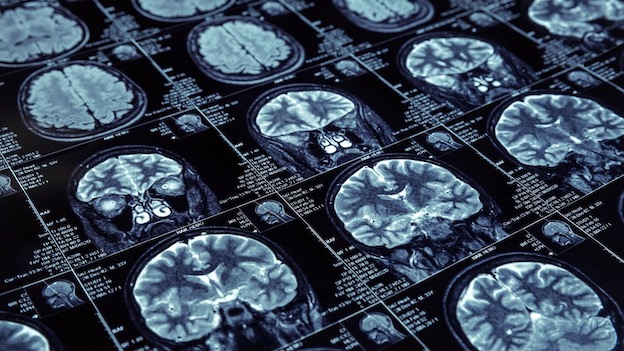

PRAY - 11-10-2022 --Si è svolto a Pray presso il Salone Teatro Polivalente, un importante il convegno da titolo “PARLIAMONE!...PER NON DIMENTICARE” sul tema del deterioramento cognitivo, volto a fornire utili informazioni sul percorso assistenziale e di cura.